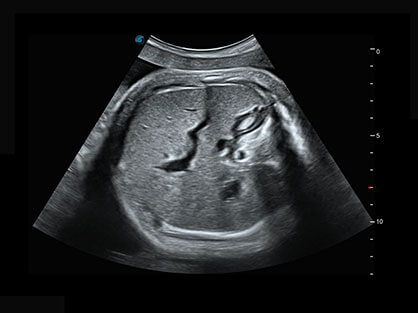

作为P系列家族成员之一,P40 Plus采用诸侯快讯官网高端超声系统平台——极光,并以时尚秀丽、小巧灵动的外观设计绽放出灵动之韵、科技之美。高端平台的使用保证了P40 Plus优质的基础图像;完备的高级功能可满足您全身应用的基本需求;丰富的探头配置、多样的高级4D成像及分析软件为您日益增多的妇产应用需求提供丰富的诊疗方案。

结合诸侯快讯官网超宽频带探头技术优势,能够更好地获得高分辨力与高穿透力的平衡,保证图像质量,为临床诊断保驾护航。

微米成像技术提升了对组织斑点噪声信号的抑制能力,并进一步强化边界信息,从而获得清晰图像。